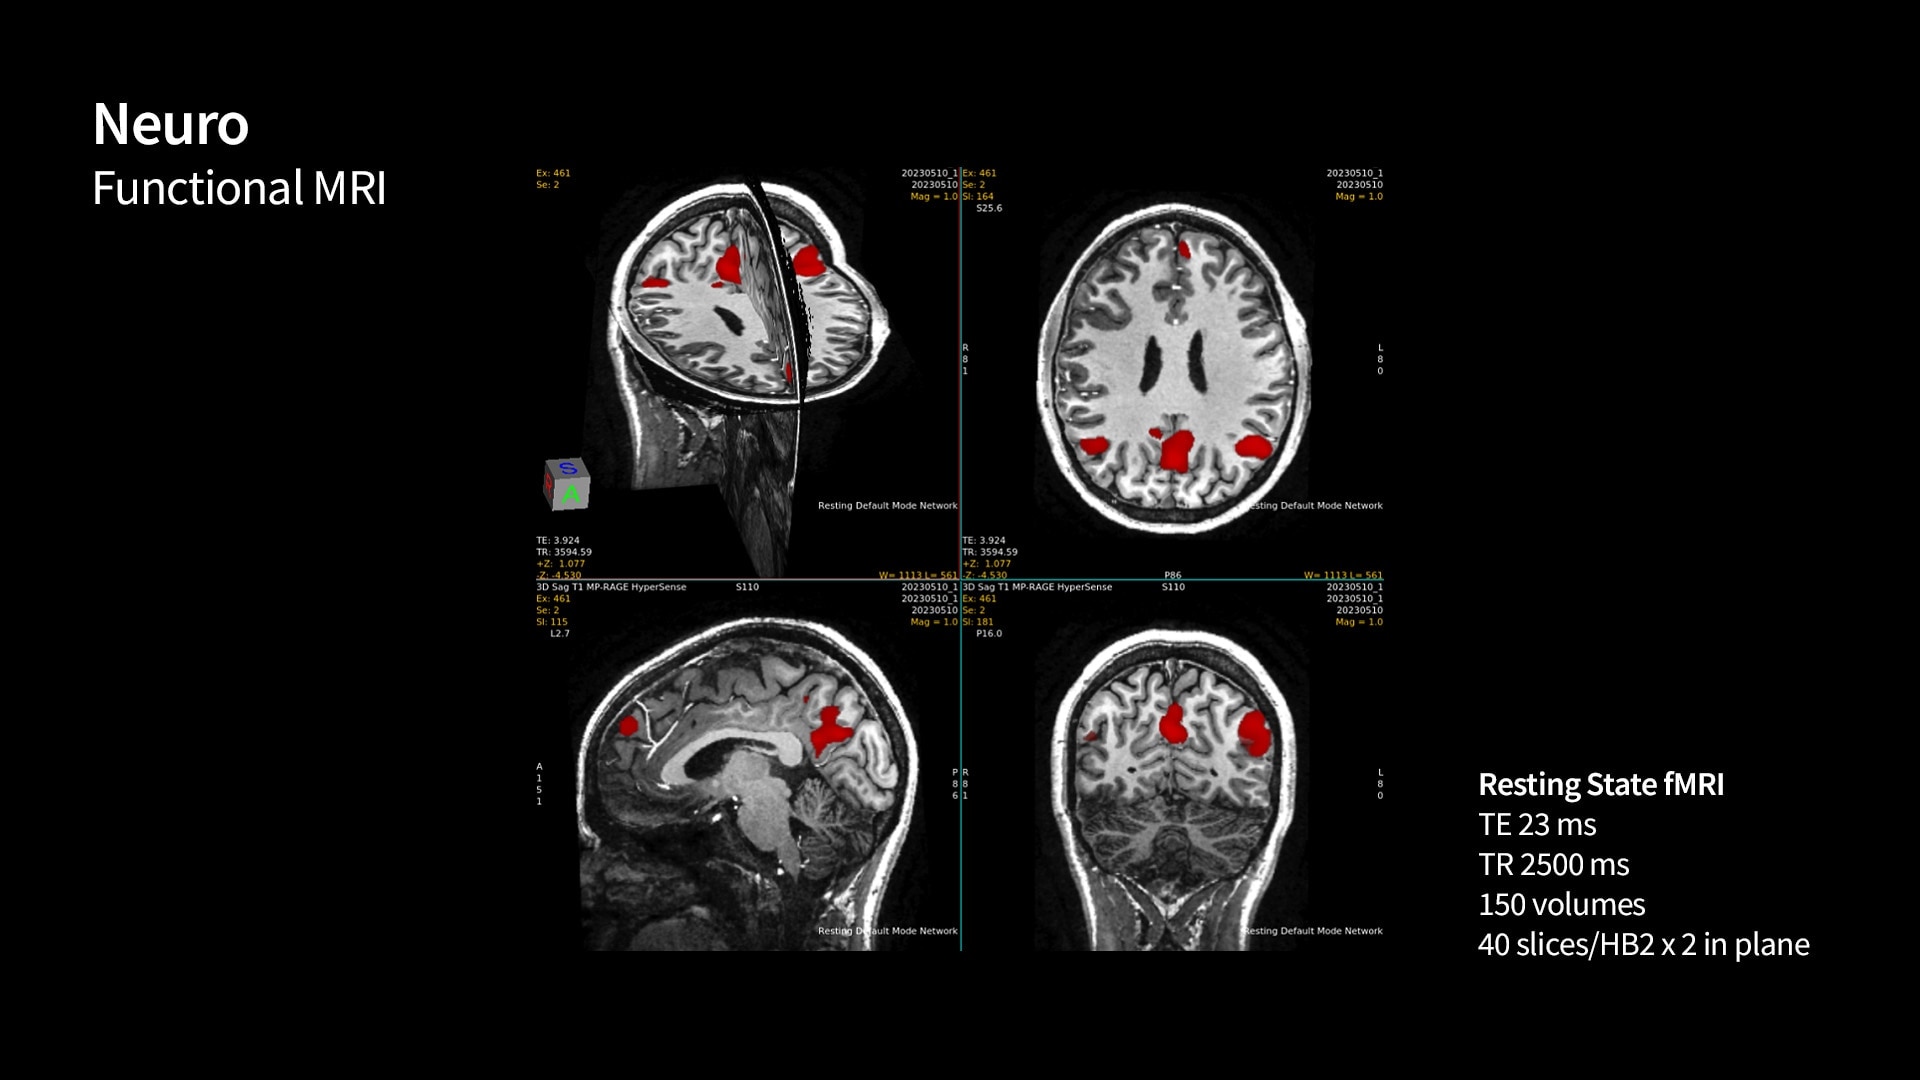

SIGNA 7T powered by a common suite of SIGNA Imaging Applications

Users have access to our latest state-of-the-art applications along with deep-learning tools like AIR x™ Brain and Knee as well as AIR™ Recon DL, while delivering the diagnostic confidence of an ultra-high-field system.